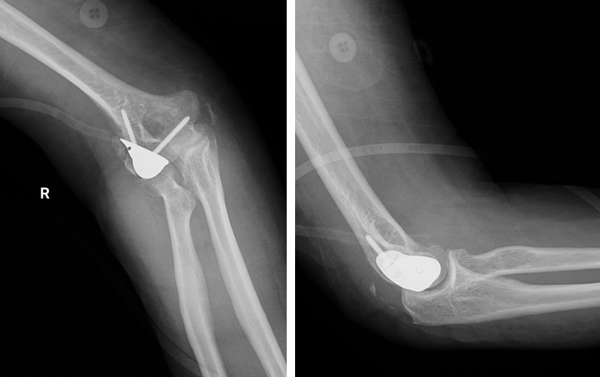

患者为一名62岁女性,因不慎摔伤导致右肘部剧痛、活动严重受限3个月,外院检查提示右侧肱骨远端骨折。为寻求进一步治疗,患者转诊至省立医院创伤中心。创伤中心李连欣主任详细检查发现,患者存在严重的骨质疏松,影像学显示肱骨小头骨折畸形愈合,近端桡、尺骨结构完整,确诊该患者为“右侧肱骨小头陈旧性粉碎性骨折”。面对骨折畸形愈合合并关节面毁损的棘手情况,传统切开复位内固定方法难以实施,且全肘关节置换手术损伤大。创伤中心团队经过探讨,最终确定采用定制化关节置换治疗方案,修复患者骨折部位、重建肘关节功能。

手术团队实行单一入路实现精准置换与韧带重建,创新性地摒弃广泛暴露的传统做法,选择右肘外侧精准切口,经肘肌与尺侧腕伸肌间隙入路,直达肱骨外侧髁骨折畸形愈合处,最大程度保护了周围健康组织。基于个体化三维影像数据,手术团队预先定制解剖吻合的人工肱骨小头假体。术中精准清除碎骨、修整畸形骨面后,手术团队按规划截骨,完美植入专属假体,并以两枚螺钉实现稳固固定。随后,手术团队仔细清理并辨识出受损的肘关节外侧副韧带及外上髁,将其整体牢固缝合至假体及肱骨外侧骨质,成功重建关节外侧稳定性,确保了术后关节韧带的完整性。

本病例定制式单纯肱骨小头精准置换,结合外上髁连同外侧副韧带整体修复治疗方案,集中体现了肘关节骨折功能修复的三大核心技术:个体化定制假体实现解剖匹配、微创单侧入路减少手术创伤、精准的外上髁韧带重建保障远期稳定。此项技术不仅为复杂肘关节损伤患者开辟了新的治疗路径,更将进一步推动创伤修复重建技术向精准化、微创化、个性化迈进。